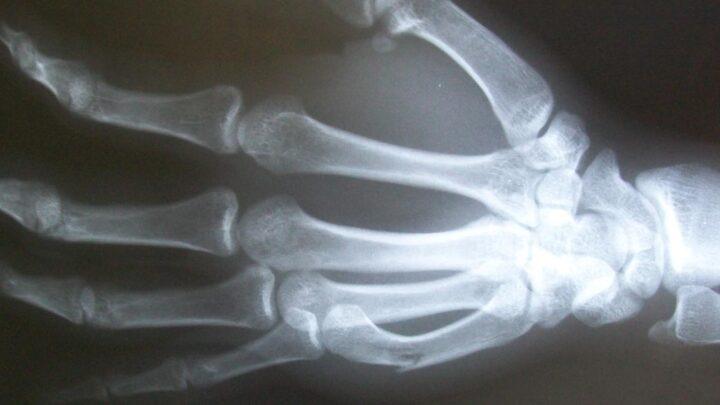

O que é o raio-x Raio-x é decorrente que a radiação X (composta por raios X) é uma forma de radiação eletromagnética. Essas radiações são…

Para que serve o curso de fraturas? Traumatologia é o termo que geralmente engloba o estudo e o tratamento de…